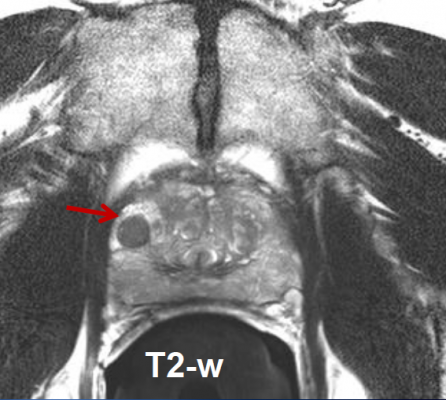

Mri S Role In Prostate Cancer Diagnosis Healthcare In Europe Com

Mri S Role In Prostate Cancer Diagnosis Healthcare In Europe Com from healthcare-in-europe.com